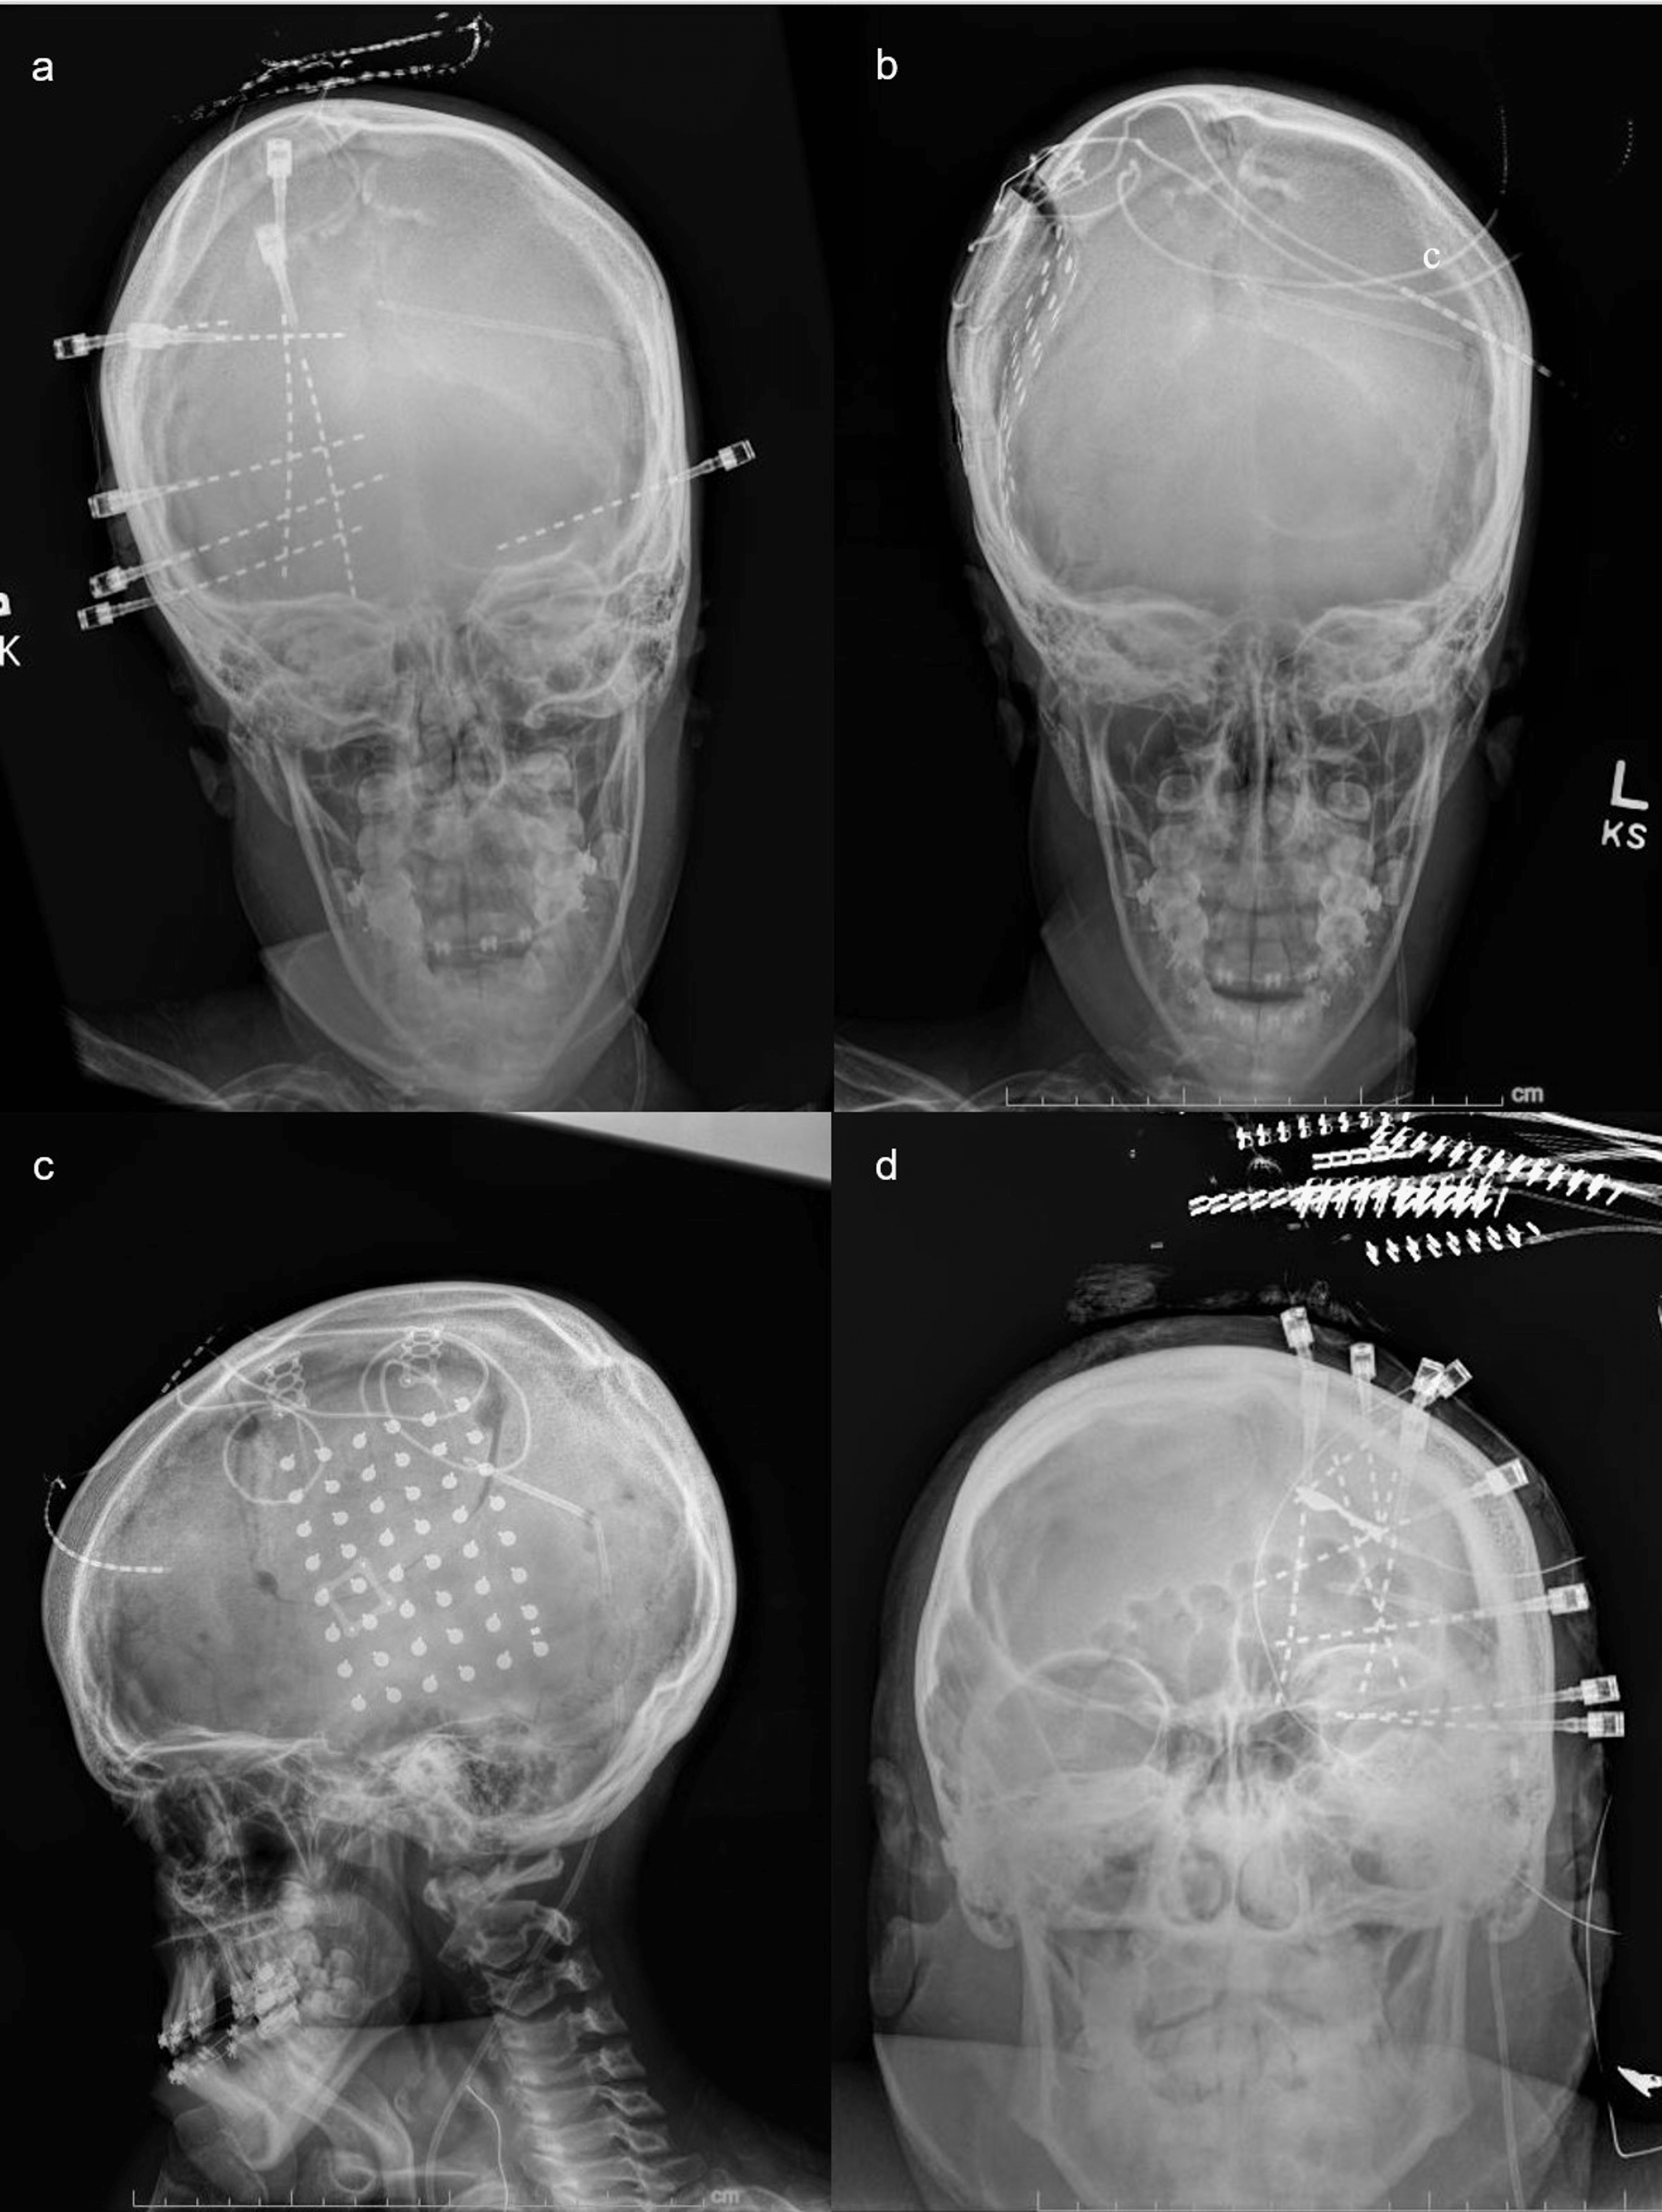

CT image of the implanted grid electrodes. The two grids (6 × 8, 4 ×6 Grid Electrodes For Epilepsy Monitoring Stereoelectroencephalography study of temporal lobe epilepsy on the left, grid study with sde of frontal lobe epilepsy with mesial. Intracranial monitoring for epilepsy has been proven to enhance diagnostic accuracy and provide localizing information for surgical. Strips and grids of electrodes are placed in the subdural space through a craniotomy or burr holes, allowing for electrocorticography. This chapter will discuss. Grid Electrodes For Epilepsy Monitoring.